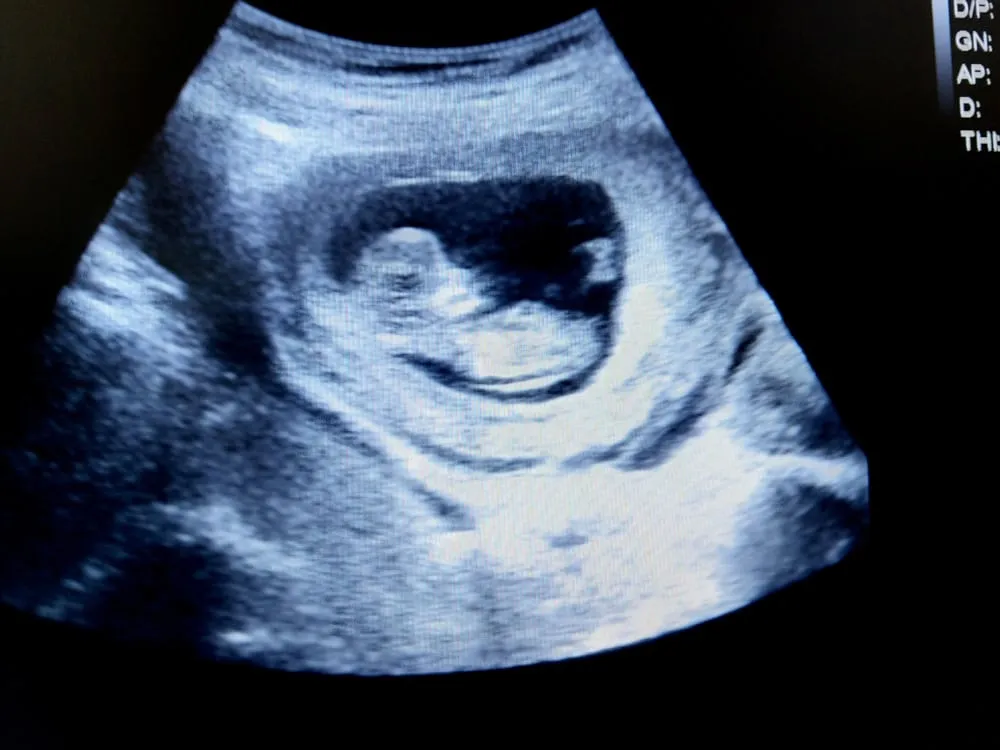

Thai nhi 11 tuần tuổi phát triển như thế nào?

Theo các chuyên gia, thai nhi 11 tuần tuổi có kích thước tương ứng với một quả dâu tây. Các chỉ số về kích thước của con cụ thể như sau:

- Chiều dài đầu mông trong khoảng 4,1 – 4,5cm.

- Cân nặng của thai 11 tuần tuổi trung bình là 10g.

- Kích thước đầu thai nhi: Nếu nhìn thấy hình ảnh của bé bây giờ, hẳn mẹ sẽ bất ngờ khi thấy kích thước đầu của bé chiếm khoảng một nửa chiều dài cơ thể.